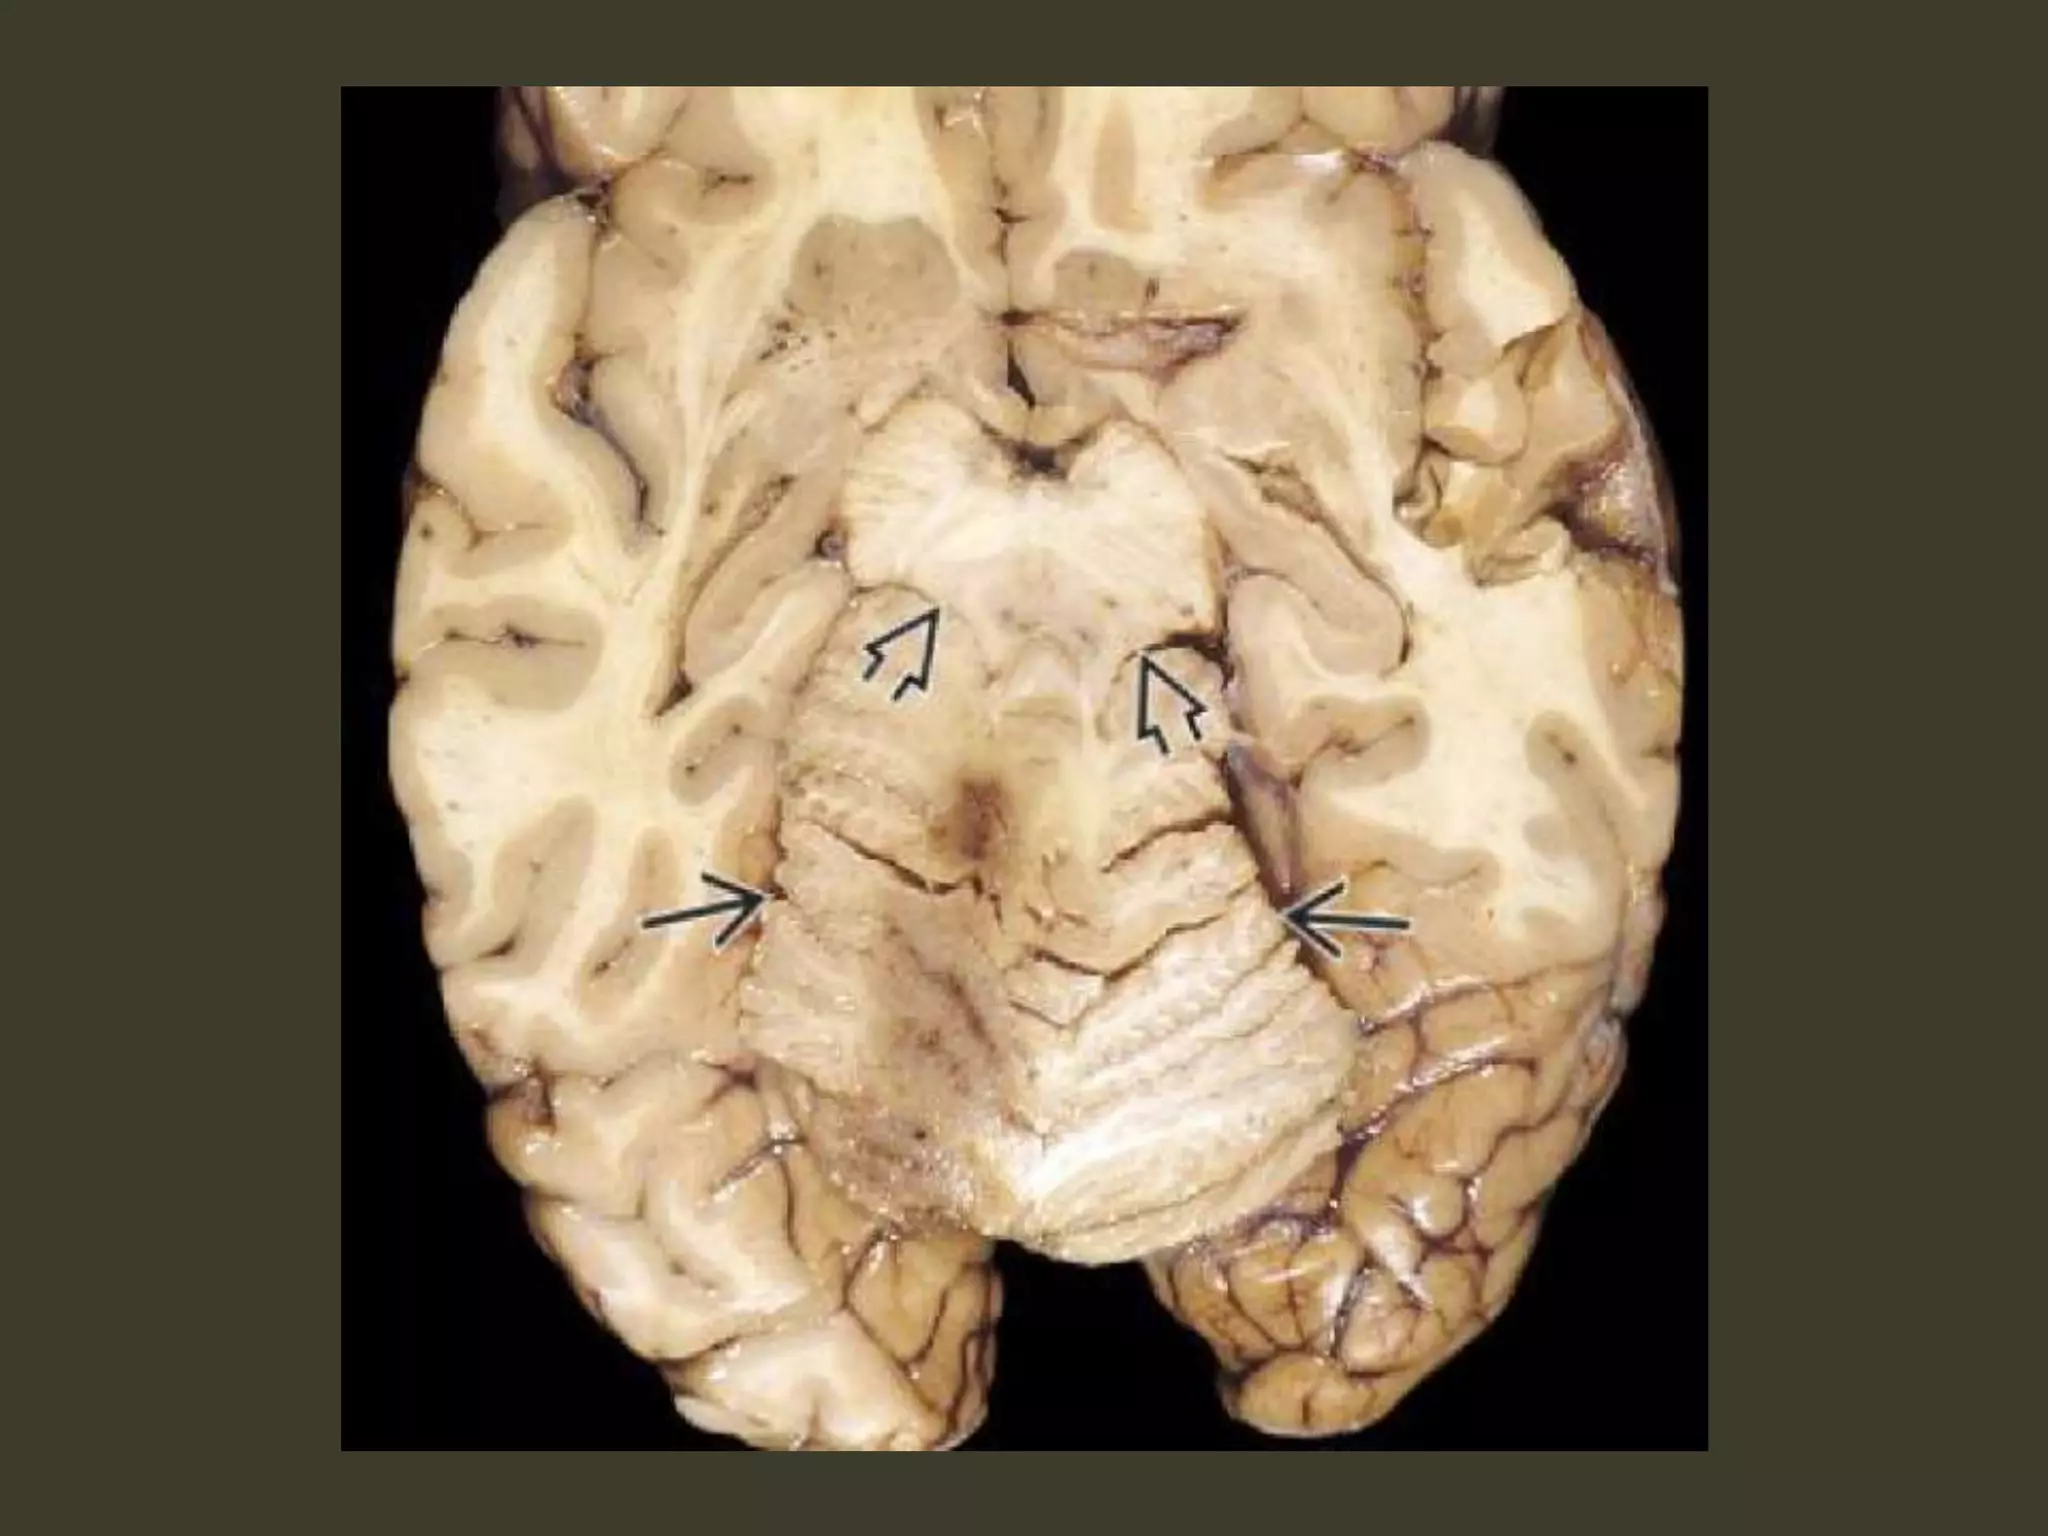

Subfalcine herniation

Subfalcine herniation: imaging

Axial and coronal images show that

•cingulate gyrus

•anterior cerebral artery (ACA)

•internal cerebral vein (ICV)

are pushed from one side to the other under the

falx cerebri.

The ipsilateral ventricle appears compressed

and displaced across the midline

Complications

• unilateral obstructive hydrocephalus

– foramen of Monro occlusion

• Periventricular hypodensity with "blurred"

margins of the lateral ventricle

– Fluid accumulates in the periventricular white

matter

• When severe, the herniating ACA can be

pinned against the inferior "free" margin of

the falx cerebri

🡪 secondary infarction of the cingulate gyrus